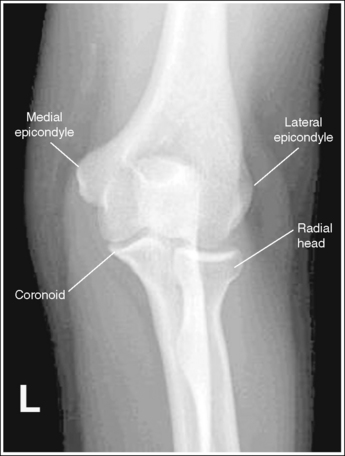

The elbow is positioned in an AP projection. The medial and lateral humeral epicondyles are demonstrated in profile at the extreme medial and lateral edges of the distal humerus, and the radial head is superimposed over the lateral aspect of the proximal ulna by approximately 0.25 inch (0.6 cm). The coronoid process is demonstrated on end.

• An AP projection of the elbow is obtained by supinating the patient's hand and externally rotating the forearm and humerus until an imaginary line drawn between the humeral epicondyles is parallel with the IR (Figure 4-67). This positioning places the proximal radius anterior to the ulna.

• Detecting elbow rotation. Rotation of the elbow is a result of poor humeral epicondyle positioning and can be identified on an image when (1) the epicondyles are not visualized in profile, (2) the radial head is demonstrated with more or less than 0.25 inch (0.6 cm) superimposition of the ulna, and (3) the coronoid process is seen in profile. The smaller, lateral humeral epicondyle is more sensitive to rotation, moving out of profile with only a slight degree of elbow rotation. If the epicondyles are not demonstrated in profile, evaluate the degree of radial head superimposition of the ulna to determine how to reposition for an AP projection. If more than 0.25 inch (0.6 cm) of radial head is superimposed over the ulna, the elbow has been internally rotated (see Image 74). If less than 0.25 inch (0.6 cm) of the radial head is superimposed over the ulna, the elbow has been externally rotated (see Images 75 and 76).

The radial tuberosity is demonstrated in profile medially, and the radius and ulna are parallel.

• The alignment of the radius and ulna is determined by the position of the humerus and the wrist. When the humerus is positioned with the humeral epicondyles parallel with the IR, the radial and ulnar relationship can be adjusted with wrist rotation. For an AP projection of the elbow, the hand and wrist should also be positioned in an AP projection by supinating the hand. This positioning places the radial tuberosity medially in profile and eliminates crossing of the radius and ulna. As the hand and wrist are pronated, the radius crosses over the ulna, and the radial tuberosity is rotated posteriorly, out of profile (see Image 77).

The capitulum-radius joint is open, the radial head articulating surface is not demonstrated, the olecranon process is situated within the olecranon fossa, and the coronoid process is demonstrated on end.

• You must use accurate central ray placement and position the forearm parallel with the IR to obtain an open capitulum-radius joint space. When the central ray is centered proximal to the elbow joint space, the capitulum is projected into the joint; when the central ray is centered distal to the elbow joint, the radial head is projected into the joint space (see Image 78). Poor central ray placement also distorts the radial head, causing its articulating surface to be demonstrated. The degree of joint closure depends on how far the central ray is positioned from the elbow joint. The farther away from the joint the central ray is centered, the more the capitulum-radial joint space is obscured and the more the radial head articulating surface is demonstrated.

The elbow has been internally rotated 45 degrees. The coronoid process, the trochlear notch, and the medial aspect of the trochlea are demonstrated in profile. The trochlear-coronoid process articulation is open, and the radial head and neck are superimposed over the ulna.

• An accurately positioned internally rotated AP oblique elbow projection is obtained by placing the arm in an AP elbow projection and then internally rotating the hand and humerus until the humeral epicondyles are at a 45-degree angle to the IR (Figure 4-74). When the elbow obliquity is correct, the coronoid process is demonstrated in profile and the radial head and tuberosity are superimposed over the ulna. If the humeral epicondyles are at less than 45 degrees of obliquity, the radial head is demonstrated lateral to the coronoid process and does not entirely superimpose the ulna (see Image 83). If the humeral epicondyles are at more than 45 degrees of obliquity, the radial head is partially visualized anterior to the coronoid process (see Image 84).

The elbow has been externally rotated 45 degrees. The capitulum and radial tuberosity are demonstrated in profile, the radial head, neck, and tuberosity are visualized without superimposing the ulna, and the radioulnar articulation is demonstrated.

• Accurate positioning for an externally rotated AP oblique elbow projection is achieved by positioning the arm in an AP projection and then externally rotating the humerus and forearm until the humeral epicondyles form a 45-degree angle with the IR (Figure 4-75). This positioning rotates the radius away from the ulna, demonstrating it without superimposition. If the humeral epicondyles are at less than 45 degrees of obliquity, the radial head and tuberosity still partially superimpose the ulna (see Image 85). If the humeral epicondyles are at more than 45 degrees of obliquity, the coronoid process is partially superimposed over the radial head, and the radial neck and tuberosity are free of superimposition; the radial tuberosity is no longer in profile (see Image 86).